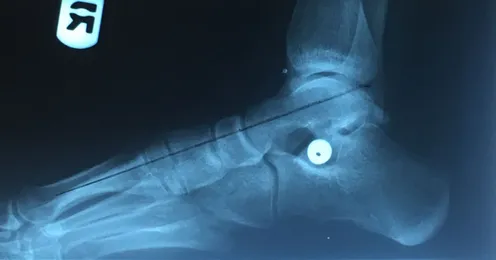

Pre and Postop X-rays Subtalar Joint Implant (Below)

Patient JD

Pre and Postop Subtalar Implant and Percutaneous Achilles Lengthening Below. The first pics show wedging of the distal tibia physis causing ankle valgus due to constant pressure caused by the severity of the flatfoot (JT)